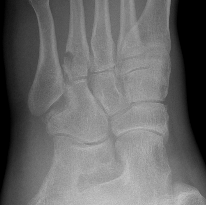

Xray

cuboid Cuboid

CT

cubcubcub